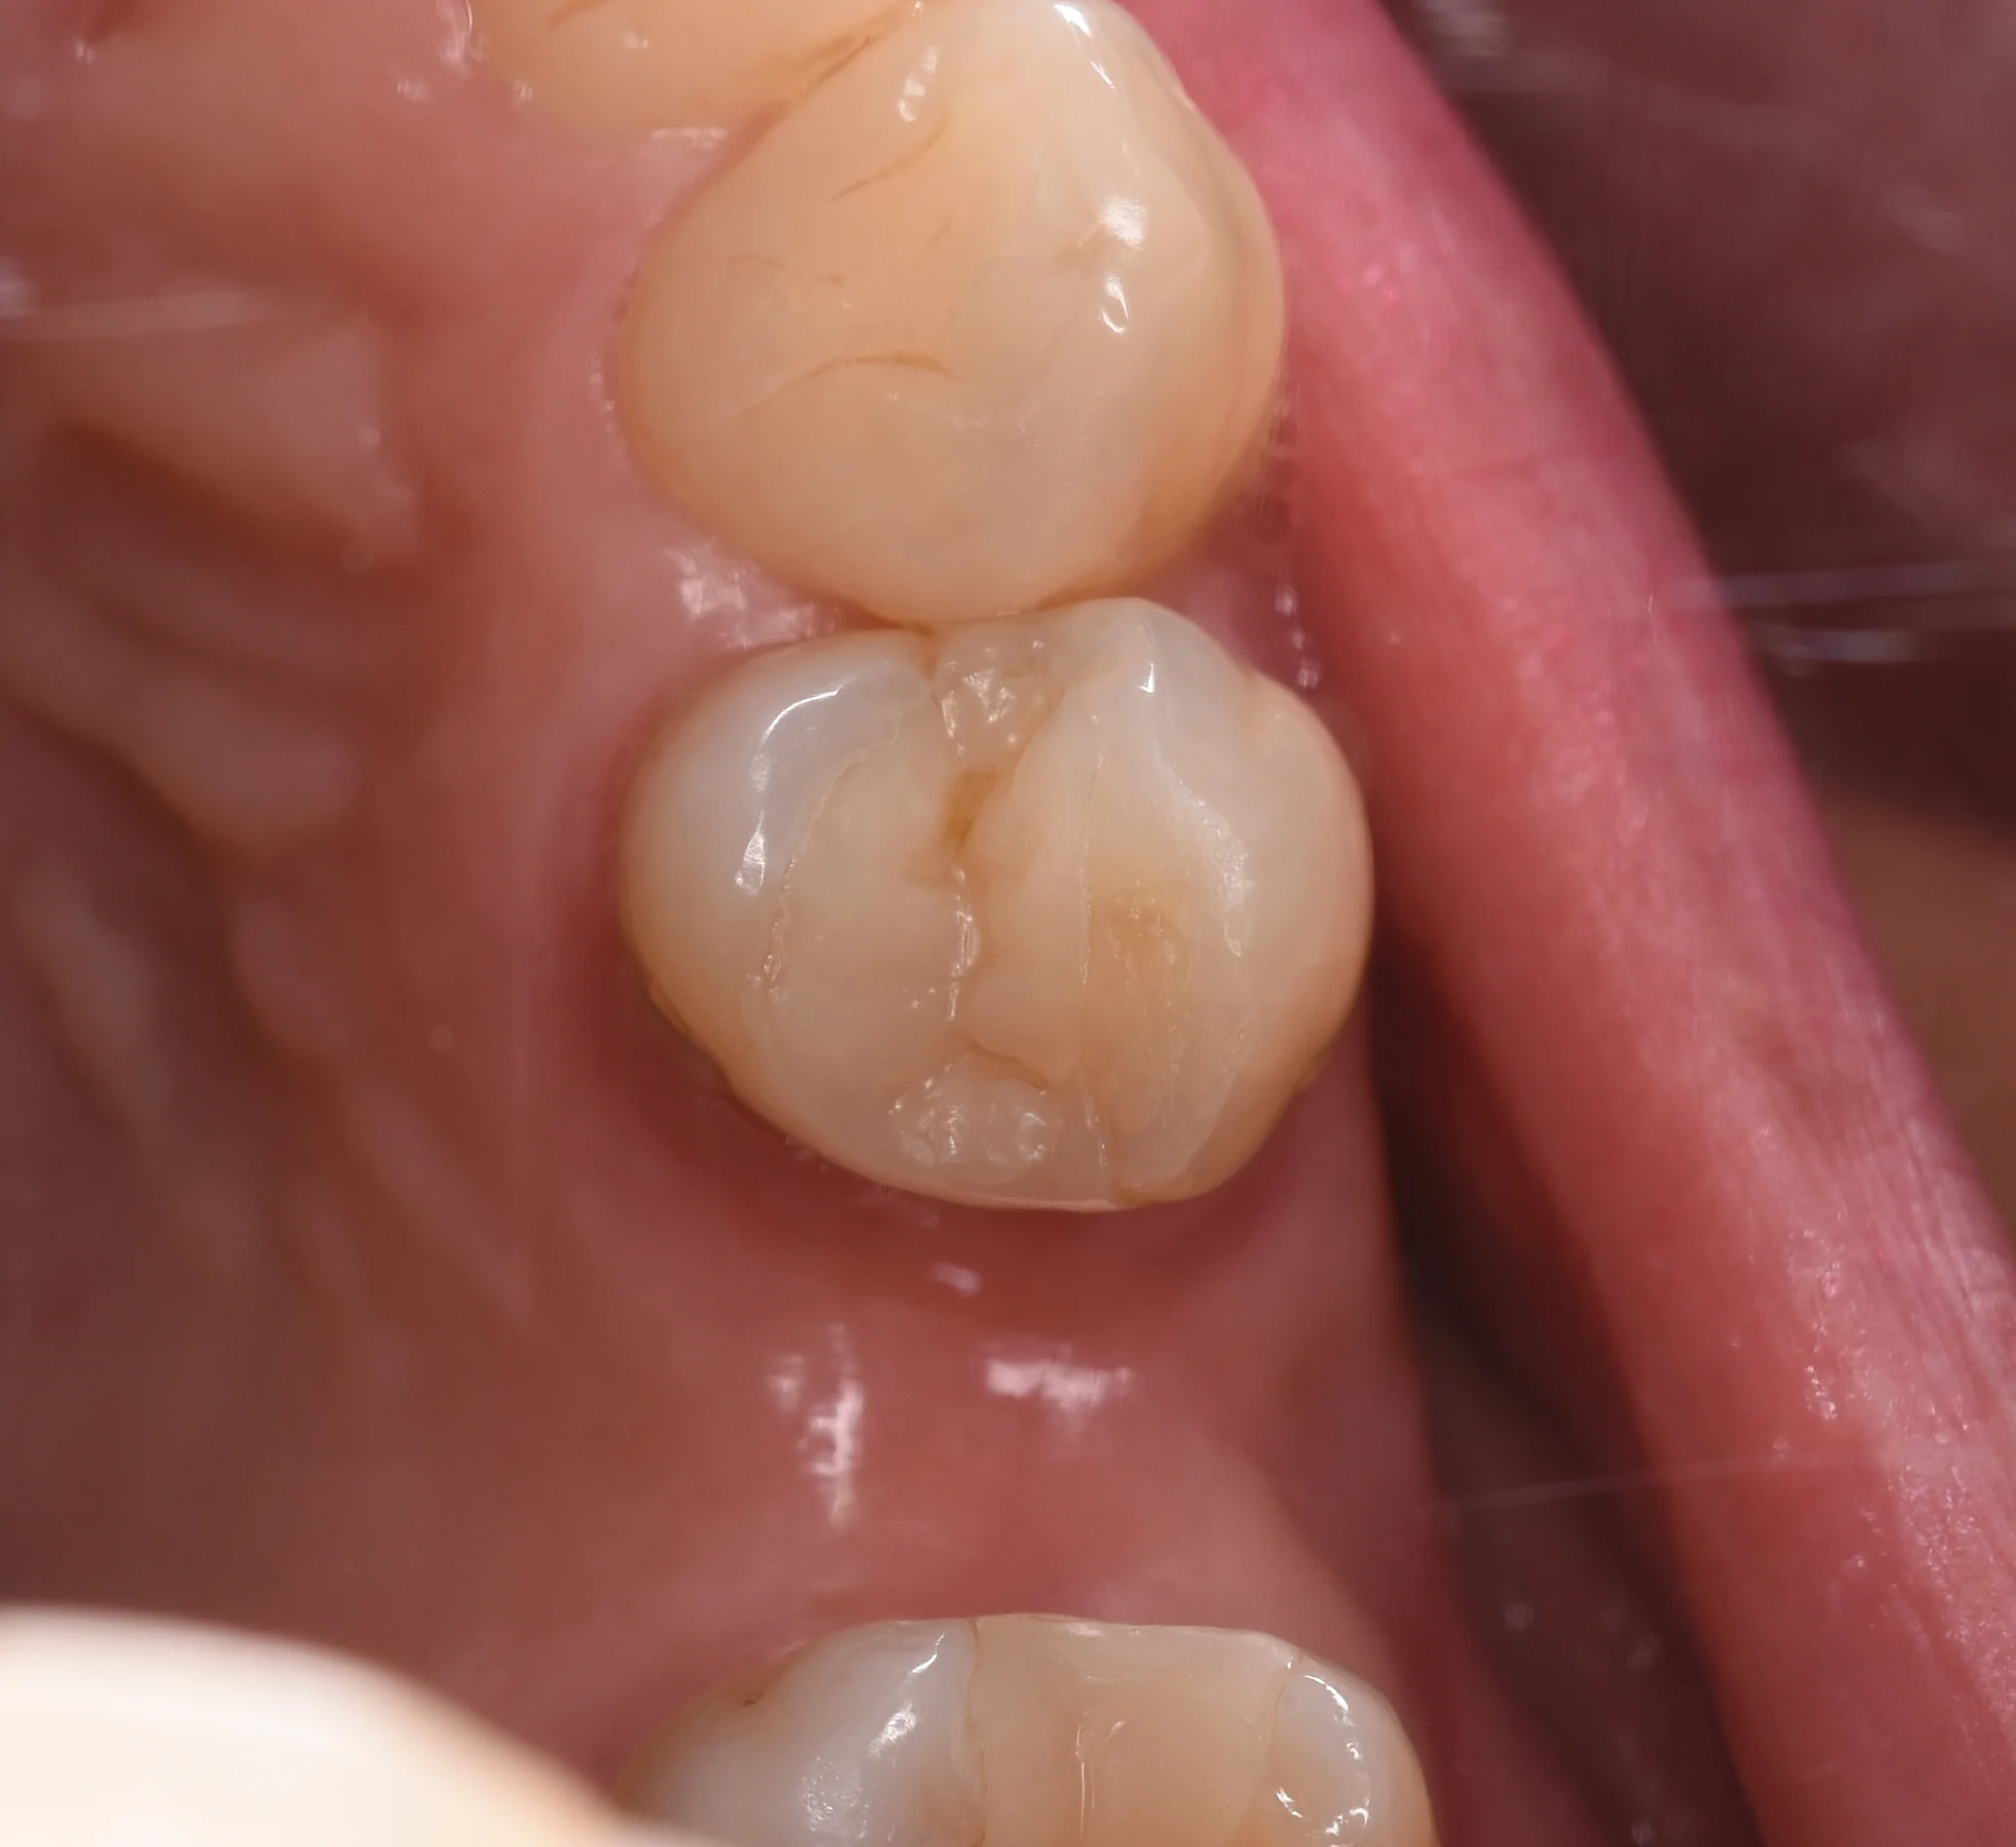

まずは4年前と同じアングルで撮影したのをアップします。

やはり術後直後に比べると劣化のため色のギャップがわかりやすくなっていますね。

とはいえ、形態もしっかりと残っていますし、引っかかりなどがあるわけではないです。

噛み合わせの変化と共にジリジリすり減っていってくれているので、歯に対してのダメージも少なく済んでいますね。